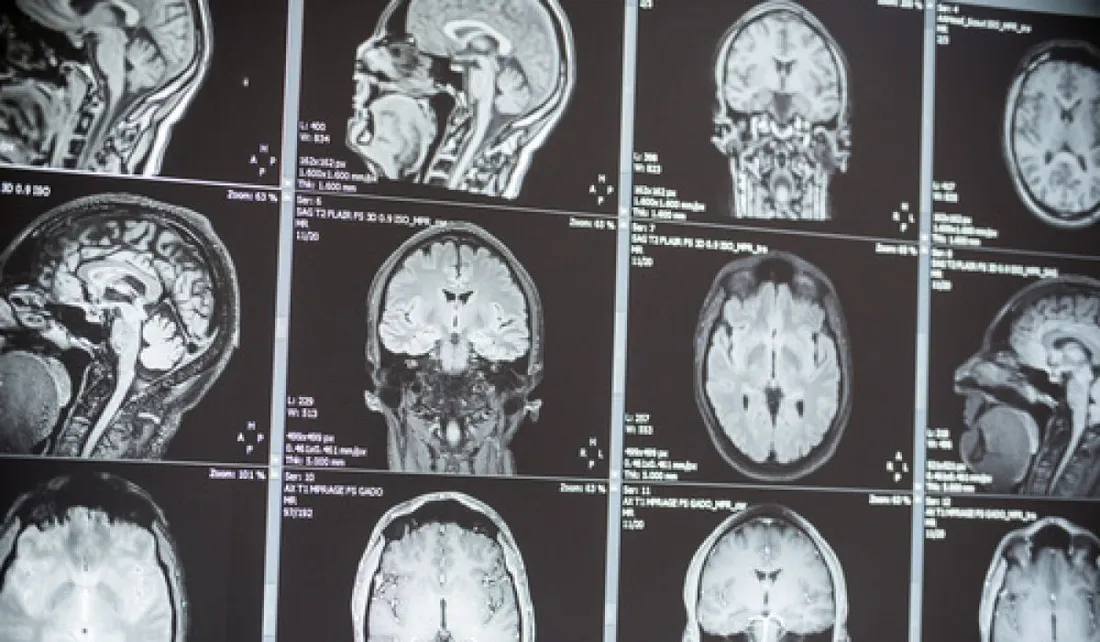

Un chirurgien et un neurologue castrais se mobilisent pour obtenir une deuxième IRM à Castres. En toile de fond, la problématique de la désertification médicale.

Actuellement, seul l'hôpital du Pays d'Autan dispose du matériel nécessaire à l'IRM et ces deux médecins, qui exercent à la clinique du Sidobre, s'inquiètent. Il faut en effet environ deux mois et demi pour obtenir un rendez vous. Selon eux, un nouvel appareil est indispensable pour le bassin castrais. Ils en appellent à l'Agence Régionale de Santé, qui délivre les autorisation.